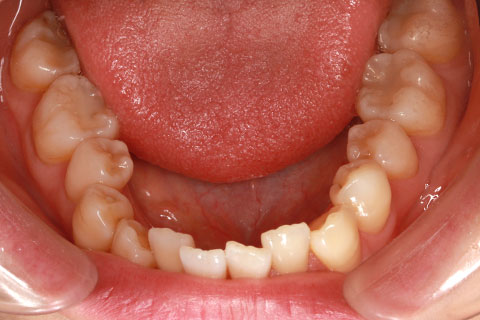

ハーフリンガル矯正3:上の歯のみ舌側矯正で治療(矯正期間24ヶ月)

治療前

治療中(開始直後)

治療中(開始半年後)

治療後

- 年齢・性別

- 25歳女性

- 治療期間

- 2年0ヶ月

- 抜歯

- 上下4番抜歯

- 治療費

- 110万円

- 治療内容

- 施術の副作用(リスク)

- 表側矯正と比較して、力学的な操作性が複雑なため、ボーイングエフェクトを起こしやすい。